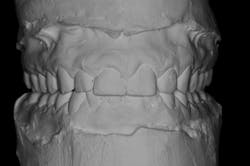

We digitally analyze our esthetics and smile design using the Dawson Diagnostic Wizard (the Dawson Academy). One of our biggest esthetic concerns in this case was caused by a functional issue. As you can see in the photos (figures 1 and 2), the patient has significantly more attritional wear on the right side versus the left. Due to the wear, the right anterior teeth have suffered from more compensatory eruption than the left, which results in uneven gingival architecture and esthetically displeasing length-to-width ratios of the anterior teeth (figures 3 and 4).

When we start to look at our occlusal shots (figures 5 and 6), it is obvious that we have some acidic erosion into dentin as well as significant wear facets from attrition. The pulp chambers of teeth Nos. 8 and 9 are now visible due to the loss of lingual tooth structure.